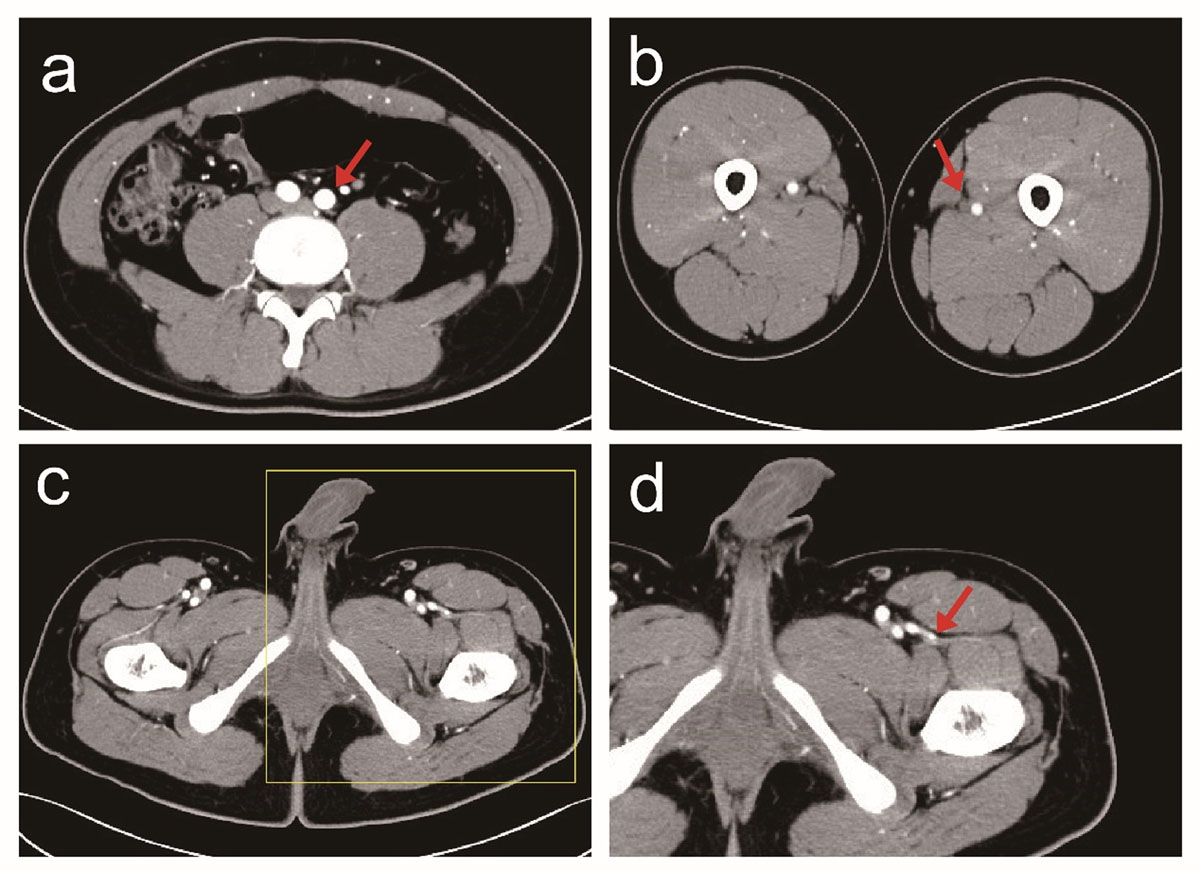

Figure 1

CTA Data Processing. a. The abdominal aorta bifurcation level; b. The mid-level of the left FA; c. The first perforating branch of the descending branch of the left lateral circumflex femoral artery (CFA), penetrated by 1 cm; d. The first perforating branch of the descending branch of the left lateral CFA, with 10 times magnified.